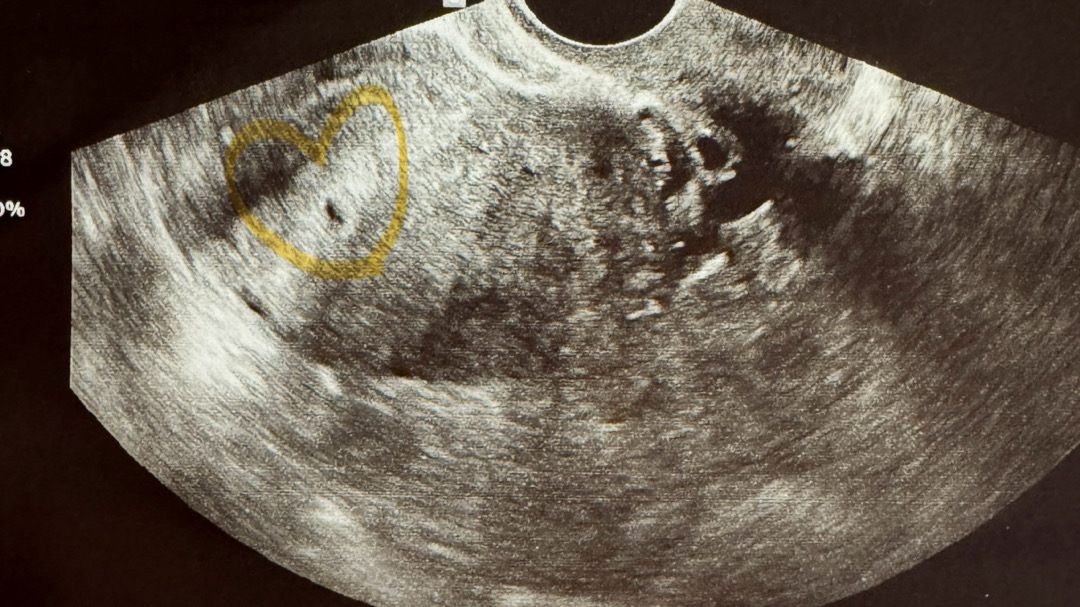

4주 6일! 쪼꼬만 아기집 봤어요 🥹

4주 6일 첫방문이고, 피검없이 바로 초음파 봤는데 아기집 아주아주 조그맣게 보고 왔어요.. 다음주 명절에 양가에 임밍아웃 할까말까 고민돼요.. 다음 진료는 명절 이후로 예약잡아주셨거든요ㅠ 그날 심장소리 들을 수도 있고 아님 깜빡임만 볼 수도 있다고 하셨어요ㅎㅎ 왠만하면 심소 듣고 양가에 소식 전하고 싶었는데 다들 언제쯤 양가+주위에 알리시나요? 다음주라도 더 커진 아기집과 난황도 보러가고 싶지만 잘 참아야겠죠!! 건강하게 잘 붙어있어주길 🤍